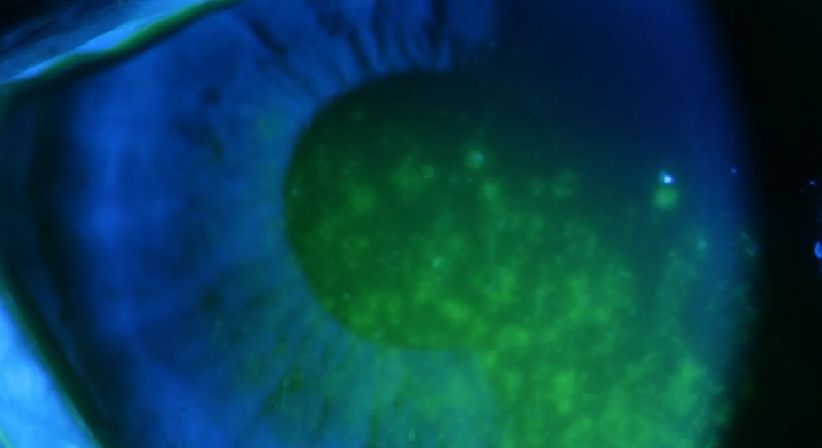

Mit dem Begriff „Trockenes Auge“ wird eine Benetzungsstörung der Augenoberfläche bezeichnet, die durch eine Verminderung der Tränenmenge (quantitative Tränenfilmstörung) oder durch eine veränderte Zusammensetzung der Tränenflüssigkeit (qualitative Tränenfilmstörung) hervorgerufen wird. Häufige Gründe können beispielsweise Klimaanlagen gepaart mit langer PC-Arbeit („Office-Eye Syndrom“) oder auch Medikamente (Antidepressiva) und hormonelle Umstellungen (Menopause) sein.